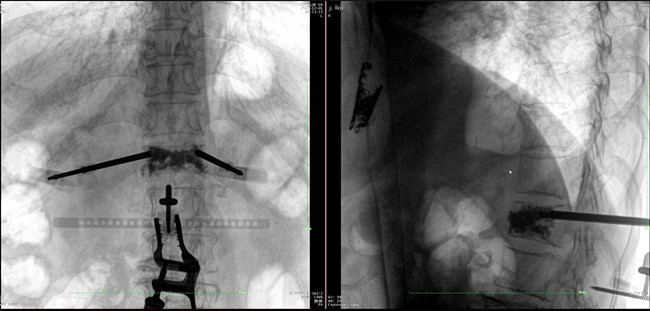

步驟二:手術(shù)實(shí)施

在病人體表切開一個(gè)長(zhǎng)1-2cm的創(chuàng)口,沿骨科機(jī)器人的機(jī)械臂定位點(diǎn)方向?qū)⒖耸厢槍?dǎo)向套筒,通過創(chuàng)口送至病灶椎體處,并沿套筒方向打入克氏針進(jìn)行定位。沿導(dǎo)針插入工作套管,取出導(dǎo)針,完成球囊擴(kuò)張后,通過骨水泥注入器準(zhǔn)確地在骨折部位緩慢注入骨水泥,幫助其恢復(fù)椎體的形狀和強(qiáng)度。

? 手術(shù)效果確認(rèn)

*骨水泥置入效果良好

良好的臨床使用體驗(yàn)源于普愛醫(yī)療骨科機(jī)器人導(dǎo)航系統(tǒng)和醫(yī)生的完美配合。亞毫米級(jí)的準(zhǔn)確定位、直觀的術(shù)前規(guī)劃和機(jī)械臂的執(zhí)行,使醫(yī)生無需擴(kuò)大創(chuàng)口進(jìn)行傷椎入針路徑定位,僅需術(shù)前三維重建即可全方位了解傷椎位置及穿刺路徑,除了極大的提高了一次性穿刺成功率,也大幅降低了手術(shù)對(duì)醫(yī)生經(jīng)驗(yàn)的要求,手術(shù)上手難度更低。